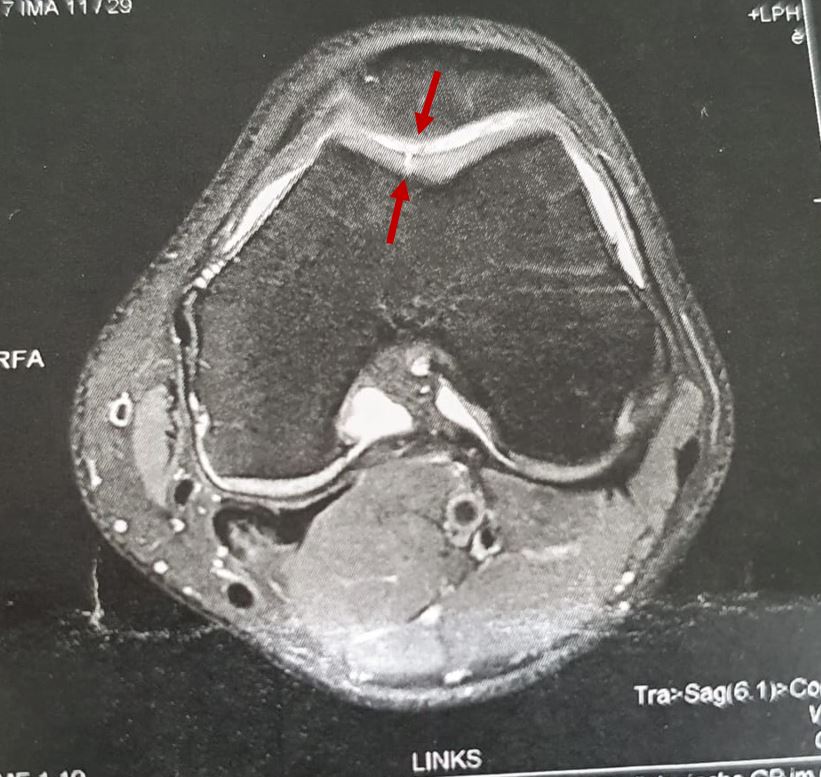

Ich hatte auf einmal Schmerzen im Knie nach einem Urlaub in Sardinien und dieser wurde in den anschliessenden Wochen nach Belastungen wie Fussballtraining und Fitnessuebungen immer groesser, sodass ich mich auf dem Weg zu meinem Sportarzt gemacht habe. Dieser hat mich sofort zum Radiologen/ MRT geschickt. Die darauffolgenden Bilder waren eindeutig. Ein kleiner Riss im Knorpel unter der Kniescheibe, welcher bis auf den Knochen durchgerissen ist (Knorpelschaden 4. Grades; Bilder folgen). Der ehemalige Mannschaftsarzt eines Fussball Bundesligisten verwies sofort auf die Mikrofrakturierung (MF), welche vor allem bei kleinen Knorpelschaeden 4. Grades bei jungen Menschen mit noch gesunden darum liegendem Knorpelgeweben angewendet wird. Eine Zweitmeinung beim naechsten noch aktiven Bundesliga-Mannschafsarzt bestätigte diese Behandlungsmethode und mir wurde langsam klar, dass es jetzt ernst wird.

MRT Bild (Knorpelriss unter der Patella)